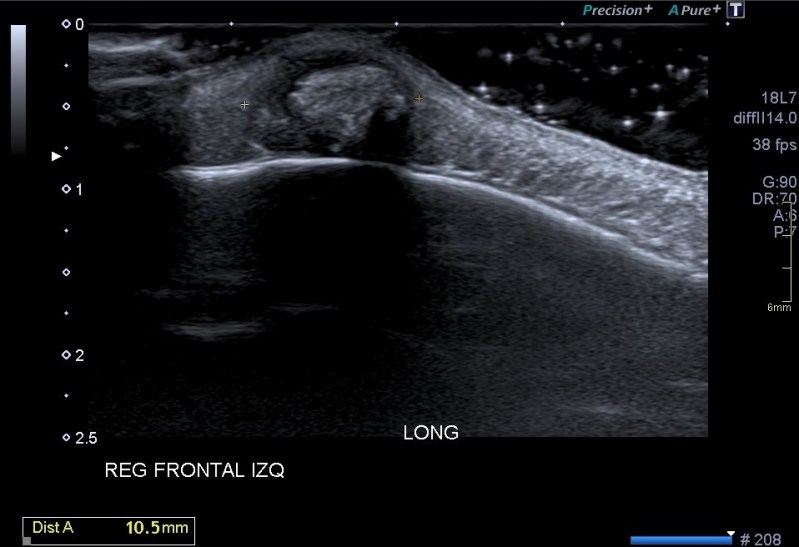

Lo primero que quiero que tengas en cuenta es la localización del bulto, ves que es supersuperficial. Para estudiar este tipo de lesiones lo que debes hacer es tener una buena capa de gel sobre el tumor. Esto se hace con efecto de apoyar la sonda sobre el gel y no sobre la piel para no deformar la lesión, así que es muy importante la técnica y pericia de la operadora que esté ejecutando el estudio.

Lo segundo es localizarlo perfectamente en su ubicación, y ver a qué planos pertenece, si está tocando o no la estructuras que están a su alrededor. En el caso de esta lesión vemos que está en justo debajo de la piel, en el escaso espesor de tejido celular subcutáneo que existe en la región frontal, que es donde la mujer tenía este tumor.

Tercero y último. Ahora lo medimos y lo estudiamos ecográficamente, acotándolo. La semiología es importante, en este caso, el tumor tiene un aspecto hipoecogénico, pero en el centro es hiperecogénico, pero además, dentro de esta hiperecogenicidad existe un grado más de hiperecogenicidad perteneciente a una calcificación grosera. Sus bordes son definidos y con la salvedad de las zonas de calcio, el tumor transmite bien. Su aspecto es heterogéneo, no presenta vascularización, la que ves en la imagen es artefacto de aliasing provocado por el calcio de la lesión.

En estos casos donde el tumor está tan cerca del hueso hay que asegurarse de que éste está indemne. Se demuestra que la lesión no afecta al hueso y que está circunscrita al ámbito puramente subcutáneo.